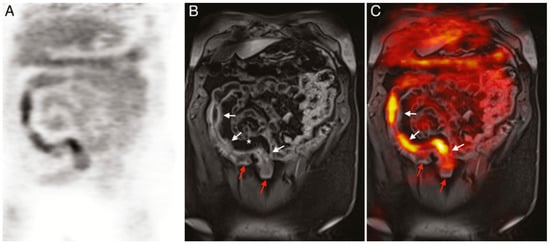

- Catalano, O.A.; Wu, V.; Mahmood, U.; Signore, A.; Vangel, M.; Soricelli, A.; Salvatore, M.; Gervais, D.; Rosen, B.R. Diagnostic Performance of PET/MR in the Evaluation of Active Inflammation in Crohn Disease. Am. J. Nucl. Med. Mol. Imaging 2018, 8, 62–69. [Google Scholar]

- Le Fur, M.; Zhou, I.Y.; Catalano, O.; Caravan, P. Toward Molecular Imaging of Intestinal Pathology. Inflamm. Bowel Dis. 2020, 26, 1470–1484. [Google Scholar] [CrossRef]